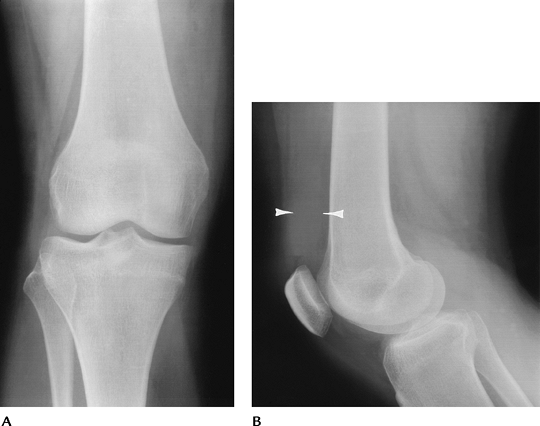

FIGURE 5-2 AP (A) and lateral (B) radiographs of a bipartite patella (arrow).

|